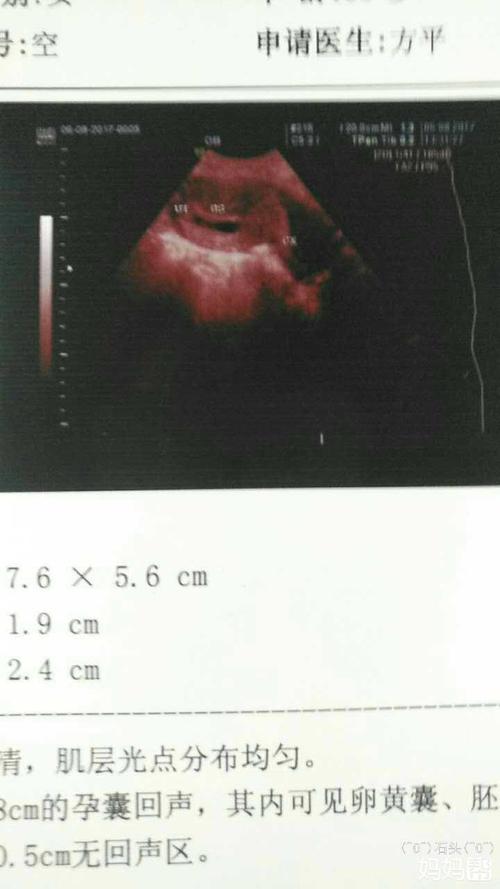

32天孕囊大小图片

32天孕囊大小图片,怀孕4周胎儿大小图片

怀孕32天孕囊b超图